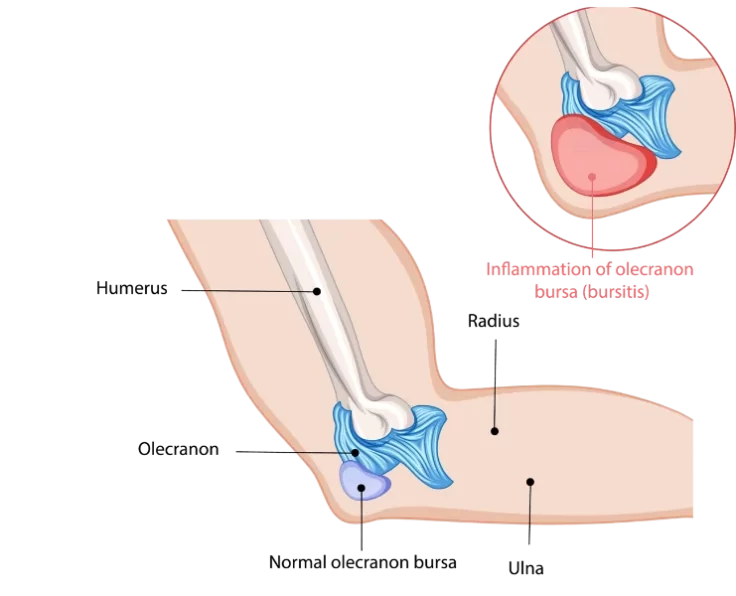

Terrible Triad in Elbow

Three injuries are combined in a horrific triad: dislocation of the elbow, radial head fracture, and coronoid fracture.

Elbow Arthroscopy OK Procedure

The operation is used to alleviate pain, eliminate locking, and increase elbow joint mobility. We do this operation as an arthroscopic procedure, despite the fact…

Elbow Arthroscopic Capsular Release

Loss of motion in the elbow joint can be caused by a variety of factors, the most common of which is elbow trauma.

Elbow Arthroscopic Debridement

Arthroscopic debridement of the elbow is a treatment procedure used to examine, diagnose, and correct abnormalities within the elbow joint.

Elbow Arthroscopic Removal of Loose Bodies

Are you unable to totally bend or straighten your elbow? Do you have pain, stiffness, or a crunching or popping sound coming from your elbow?